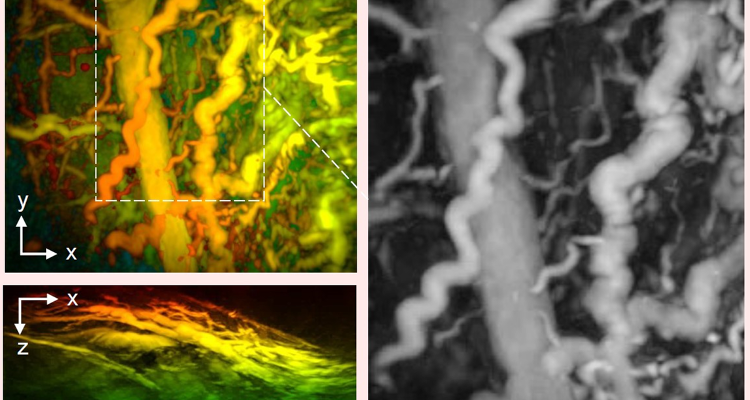

比传统方法快百倍乃至千倍 新型扫描仪实现秒级医学成像

科技日报

10月08日 09:49